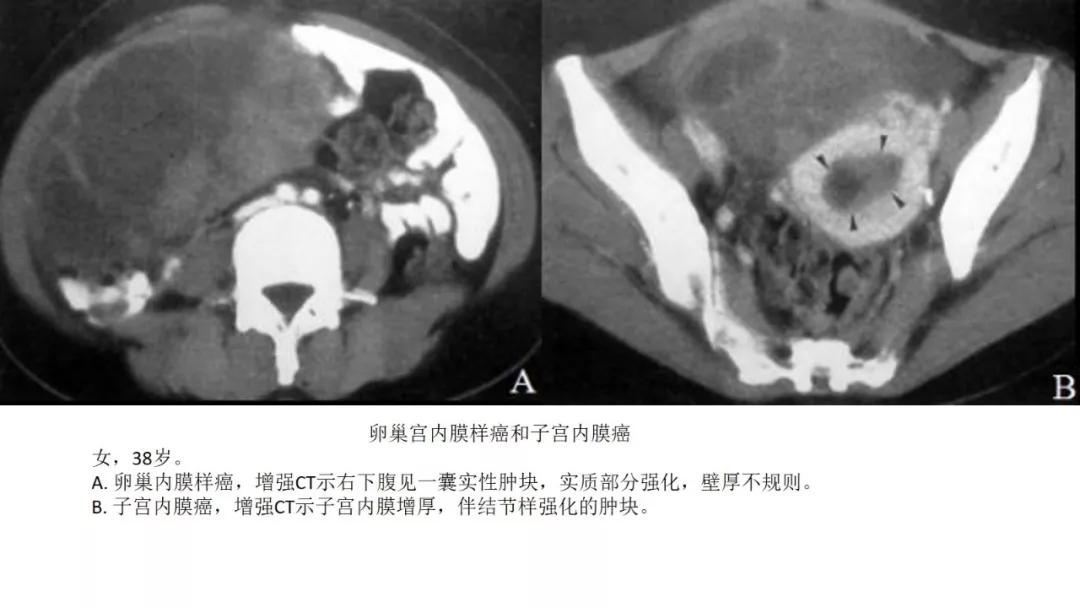

- 子宫内膜样癌与透明细胞肿瘤临床、影像表现比较类似,是微差别的上皮双胞胎

- 伴子宫内膜增厚:性索间质性肿瘤(颗粒为主)、子宫内膜样癌、透明细胞肿瘤

- 囊实性伴壁结节:透明细胞肿瘤、子宫内膜样癌